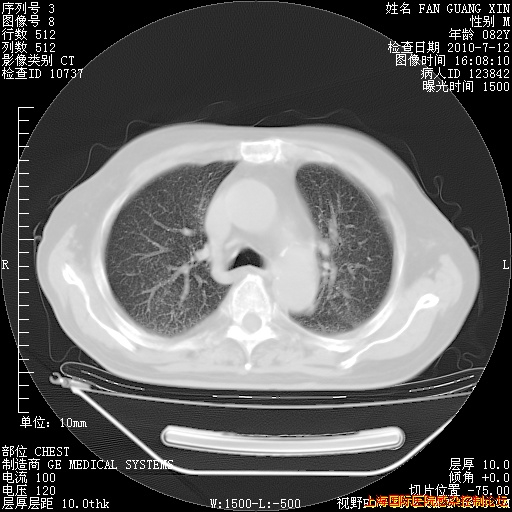

6月12日肺窗

整整相隔30天的肺部CT好像有所好转啊。甲强龙减量第3天,需要观察体温。